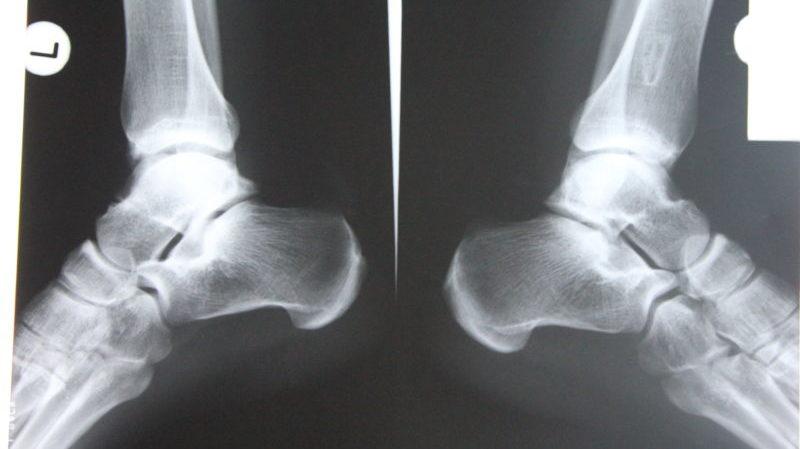

Рентгенологическое исследование основывается на том, что мягкие ткани пропускают рентгеновские лучи, в то время как твердые их поглощают. В результате мышцы и кожа на рентгеновских снимках выглядят темными, а кости – светлыми. Эта способность четко отображать костные структуры делает рентген незаменимым инструментом для диагностики заболеваний костей.

В ходе диагностики и анализа производится сопоставление полученных изображений с нормальными показателями. Описываются следующие структуры:

- Костная поверхность. Наличие разрушений может указывать на серьезное воспаление или злокачественные опухоли. Отслоение может свидетельствовать о развитии периостита. Окостенение хрящевой ткани является признаком периостоза.

- Костная ткань. Увеличение объема костной ткани может говорить о воспалительных процессах или нарушениях кровообращения, в то время как уменьшение указывает на атрофию, вызванную недостаточной физической активностью.

- Структура кости. Нарушение целостности может быть признаком трещины или перелома. Снижение количества костных балок указывает на остеопороз, а увеличение плотности – на остеосклероз. Рассасывание или некроз костной ткани свидетельствует об остеолизе.

- Суставная щель. Ее сужение может указывать на артрит, сращение – на анкилоз, наличие остеофитов – на артроз, а расширение – на разрыв связок.

- Стопа. Угол свода, превышающий или не достигающий 130°, а также высота, превышающая или не достигающая 35 мм, могут свидетельствовать о продольном плоскостопии. О поперечном плоскостопии говорит заворот большого пальца.

- Разрывы и растяжения связок. Исследование проводится в двух проекциях, часто с применением обезболивающих средств. Рентгеновские снимки при повреждении связок голеностопного сустава могут показать смещение таранной кости, скопление жидкости в области повреждения и утолщение связок. При разрыве наблюдаются смещения концов костей и увеличение щели мягких тканей.